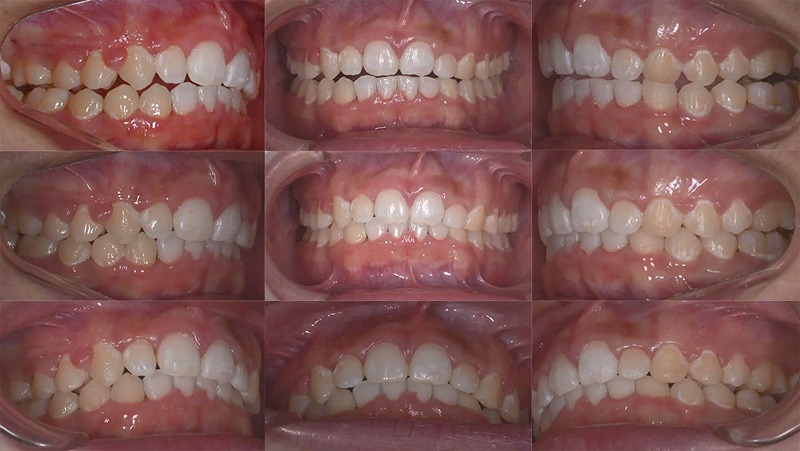

Case02前歯の凸凹を改善した症例

結婚式前に前歯の凸凹を治したいといらっしゃいました。叢生は軽度でタイムリミットは8か月でした。診査の結果、非抜歯なら十分に間に合うと診断しました。上下顎ともに少し側方拡大を行い、歯を並べました。2年後、問題なく経過しています。

ファイナル 2017.10.27

治療2年後 2019.10.12